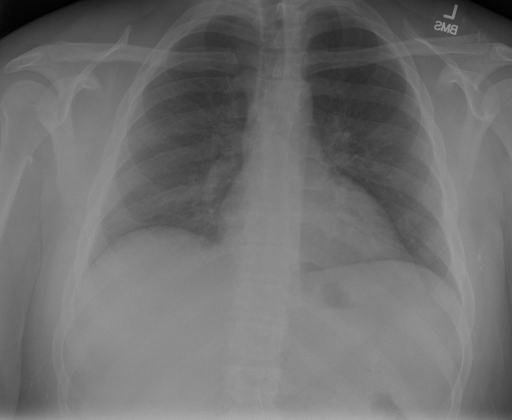

- (1)准备[诊疗报告(中文)](./data/Xray/openi-zh.json)和[X光影像](https://pan.baidu.com/s/13GBsDMKf6xBZBSHpoWH_EA?pwd=k9sh)在`data/Xray`文件夹下; - (2)开始训练: ```bash # 设置CUDA变量,主要是为了解决有时候直接训练而出现无法正确加载到显卡问题 export CUDA_VISIBLE_DEVICES=0,1,2,3 # 开始训练 bash finetune_XrayGLM.sh ``` 这里的复现过程非常简单,主要是很多过程我们都为大家准备好了,大家可以随时复现一个自己的`XrayGLM`。 ### 4.模型训练(通用) - [【官方视频教程】XrayGLM微调实践](https://www.bilibili.com/video/BV1Yh4y147gx/) - [复旦大学《大语言模型理论与实践》](https://intro-llm.github.io/) ## 效果展示 *以下效果来自于**低质量**的数据训练和权重 影像诊断: |X光影像|诊疗报告(医生)|XrayGLM| |:-|:-|:-| |![](./data/Xray/2_1.png)|根据X射线图像,心脏大小正常,肺部看起来很清晰。已经排除了肺炎、积液、水肿、气胸、腺病、结节或肿块的存在。该发现表明一切正常。换句话说,总体印象是胸部正常。|X光片显示,心脏大小正常。肺部没有气胸或胸腔积液的证据。骨骼结构看起来没有任何异常。总的来说,X光片表明没有发现急性心肺疾病的迹象。| |![](./data/Xray/2882_1.png)|X光图片显示没有扭曲的区域、可疑的骨质不透明度或胸腺积液。心脏大小轻微增大,但非常稳定。此外,没有气胸的证据,肺野也正常。总体来说,X光片显示没有急性心脏异常,但要注意轻微的心脏扩大。|X光片显示,心脏大小正常。肺部和纵隔轮廓清晰,没有气胸或胸腔积液的证据。骨骼结构完整,没有任何急性异常。| |![](./data/Xray/2577_1.png)|心影形态在正常范围内。没有急性骨质异常。有可能出现没有明显的吸水或肺实质状况的线索。没有大面积积液或气胸。有可能怀疑其有误吸或肺实质问题。为了确诊和治疗,可能需要进行适当的影像学随访。|心脏大小正常,肺部和纵隔轮廓清晰。没有急性异常或活动受限的证据。没有任何明显的气胸、胸腔积液或肺不张的迹象。此外,也没有发现任何局灶性骨质异常或其他急性疾病。| 多轮对话: |X光影像|诊疗报告(医生)| |:-|:-| |![](./data/Xray/861_1.png)|右侧主动脉突出观察到。心脏大小正常。胸部未发现明显的肺气肿、胸膜积液或可疑的肺部病变。报告指出已知右侧主动脉情况正常。| ```bash >> X光影像路径:./data/Xray/861_1.png >> 用户:这是一张什么图? >> XrayGLM:这张图片显示的是一张肺部检查的X光片。 >> 用户:请描述这张胸部X光片的诊断结果 >> XrayGLM:心脏大小正常,肺部清晰。没有急性心肺疾病的证据。 >> 用户:是否存在肺气肿? >> XrayGLM:没有肺气肿。心脏大小正常,肺部清晰。没有发现急性心肺疾病的证据。 >> 用户:平时饮食该注意什么? >> XrayGLM:饮食应该健康,均衡。建议增加蛋白质的摄入量,因为蛋白质有助于维持肌肉和骨骼的健康。多食用蔬菜、水果、全谷物以及健康的脂肪来源如橄榄油、鱼类等可以帮助获得足够的维生素和矿物质。此外,避免过度饮酒或吸烟,这些习惯可能会对心脏健康产生负面影响。 ``` ## 未来展望 1. 模型的能力更多来源于数据的支持,`OpenI-zh`作为微调数据集,其数据量足以支持研究,在更广泛的任务和性能表现上,我们认为**在大规模数据集上预训练并在高质量少量数据集上微调是一种可行的方案**; 2. 普遍意义的理解上,视觉多模态模型=视觉模型+语言模型。除了需要关注视觉模型信息与语言模型输出的搭配外,还需要**额外关注到语言模型的加强,在人机的对话中,尤其是医疗语言模型的问答上,除了专业的医疗问题回答,带有人文情怀的有温度的回答更应该是我们追寻的目标**。 3. **高精度的模型永远打不过大参数的模型**,如果在6B模型和13B模型上选择微调,请在资源充足情况下选择13B的大参数模型; ## 项目致谢 1. [VisualGLM-6B](https://github.com/THUDM/VisualGLM-6B)为我们提供了基础的代码参考和实现; 2. [MiniGPT-4](https://github.com/Vision-CAIR/MiniGPT-4)为我们这个项目提供了研发思路; 3. ChatGPT生成了高质量的中文版X光检查报告以支持XrayGLM训练; 4. [gpt_academic](https://github.com/binary-husky/gpt_academic)为文档翻译提供了多线程加速; 5. [MedCLIP](https://github.com/RyanWangZf/MedCLIP) 、[BLIP2](https://huggingface.co/docs/transformers/main/model_doc/blip-2) 、[XrayGPT](https://github.com/mbzuai-oryx/XrayGPT) 等工作也有重大的参考意义; ![](./assets/images/mpu.png) 这项工作由[澳门理工大学应用科学学院](https://www.mpu.edu.mo/esca/zh/index.php)硕士生[王荣胜](https://github.com/WangRongsheng) 、[段耀菲](https://github.com/IsBaSO4) 、[李俊蓉](https://github.com/lijunrong0815)完成,指导老师为檀韬副教授、[彭祥佑](http://www.patrickpang.net/)老师。 *特别鸣谢:[USTC-PhD Yongle Luo](https://github.com/kaixindelele) 提供了有3000美金的OpenAI账号,帮助我们完成大量的X光报告翻译工作 ## 免责声明 本项目相关资源仅供学术研究之用,严禁用于商业用途。使用涉及第三方代码的部分时,请严格遵循相应的开源协议。模型生成的内容受模型计算、随机性和量化精度损失等因素影响,本项目无法对其准确性作出保证。即使本项目模型输出符合医学事实,也不能被用作实际医学诊断的依据。对于模型输出的任何内容,本项目不承担任何法律责任,亦不对因使用相关资源和输出结果而可能产生的任何损失承担责任。 ## 项目引用 如果你使用了本项目的模型,数据或者代码,请声明引用: ```bash @misc{wang2023XrayGLM, title={XrayGLM: The first Chinese Medical Multimodal Model that Chest Radiographs Summarization}, author={Rongsheng Wang, Yaofei Duan, Junrong Li, Patrick Pang and Tao Tan}, year={2023}, publisher = {GitHub}, journal = {GitHub repository}, howpublished = {\url{https://github.com/WangRongsheng/XrayGLM}}, } ``` ## 使用许可 此存储库遵循[CC BY-NC-SA](https://creativecommons.org/licenses/by-nc-sa/4.0/) ,请参阅许可条款。